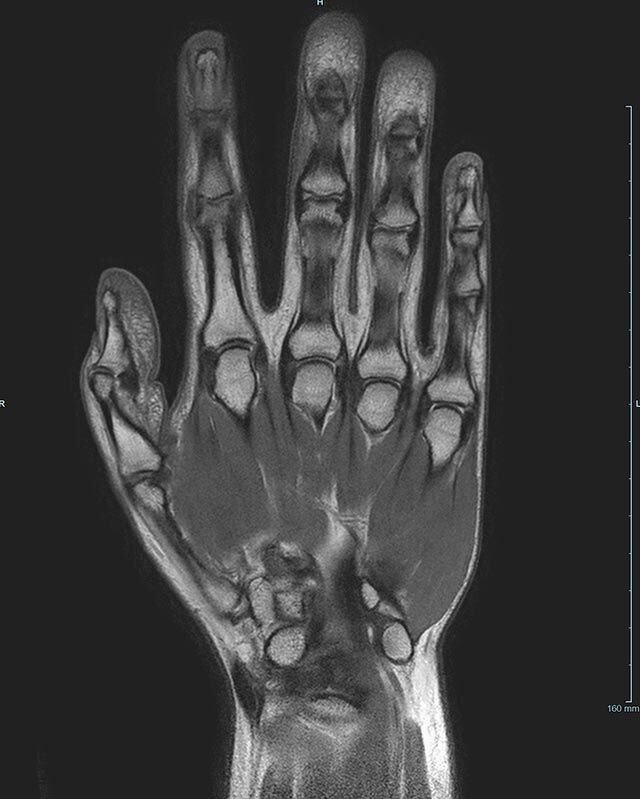

Magnetresonanztomographie (MRT)

Die Magnetresonanztomographie (MRT) wurde als bildgebendes Verfahren ab 1973 vor allem von Paul C. Lauterbur und Sir Peter Mansfield entwickelt.

In den letzten Jahren hat sich die Methode stark weiterentwickelt und in der medizinischen Diagnostik etabliert.

Im Magnetresonanztomographen liegt die zu untersuchende Person in einem starken, homogenen Magnetfeld. Dieses Magnetfeld bewirkt eine gemeinsame Ausrichtung der Wasserstoffprotonen im Körper entlang der Längsachse des Magnetfeldes. Wird nun diesen Teilchen Energie in Form von Radiowellen in einer genau abgegrenzten Frequenz zugeführt, so werden sie aus ihrer ursprünglichen Orientierung abgelenkt.

Die zugeführte Energie wird in gewebespezifischer Weise wieder abgegeben. Ein hochempfindliches Computersystem misst die unterschiedliche Energieabgabe und setzt sie in Bildinformationen um. Jede Körperregion kann somit durch Schnittbilder in allen Raumebenen oder durch dreidimensionale Rekonstruktionen mit einem exzellenten Weichteilkontrast dargestellt werden. Es besteht keine Belastung durch Röntgenstrahlen.